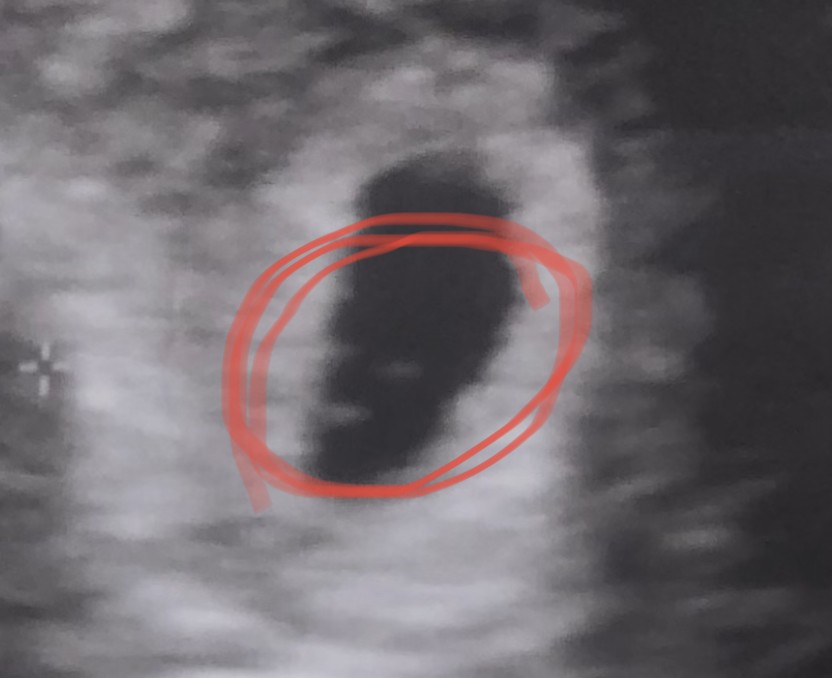

Hej dziewczyny ! Chcialabym zapytac o Wasze zdanie. Jak myślicie, te 3 kropeczki to chyba nie jest ciąża mnoga? 🤔🤔

Ginekolodzy często zakładają karte ciąży troszkę później jak już bije serduszko itd ale to na pewno zależy od lekarza. Trochę dziwne ze tak nic nie powiedziała ale może nie czuła się kompetentna dlatego pokierowała Cię do tej specjalnej poradni. Masz na usg napisaną wielkość pęcherzyka czy nie było go jeszcze widać?